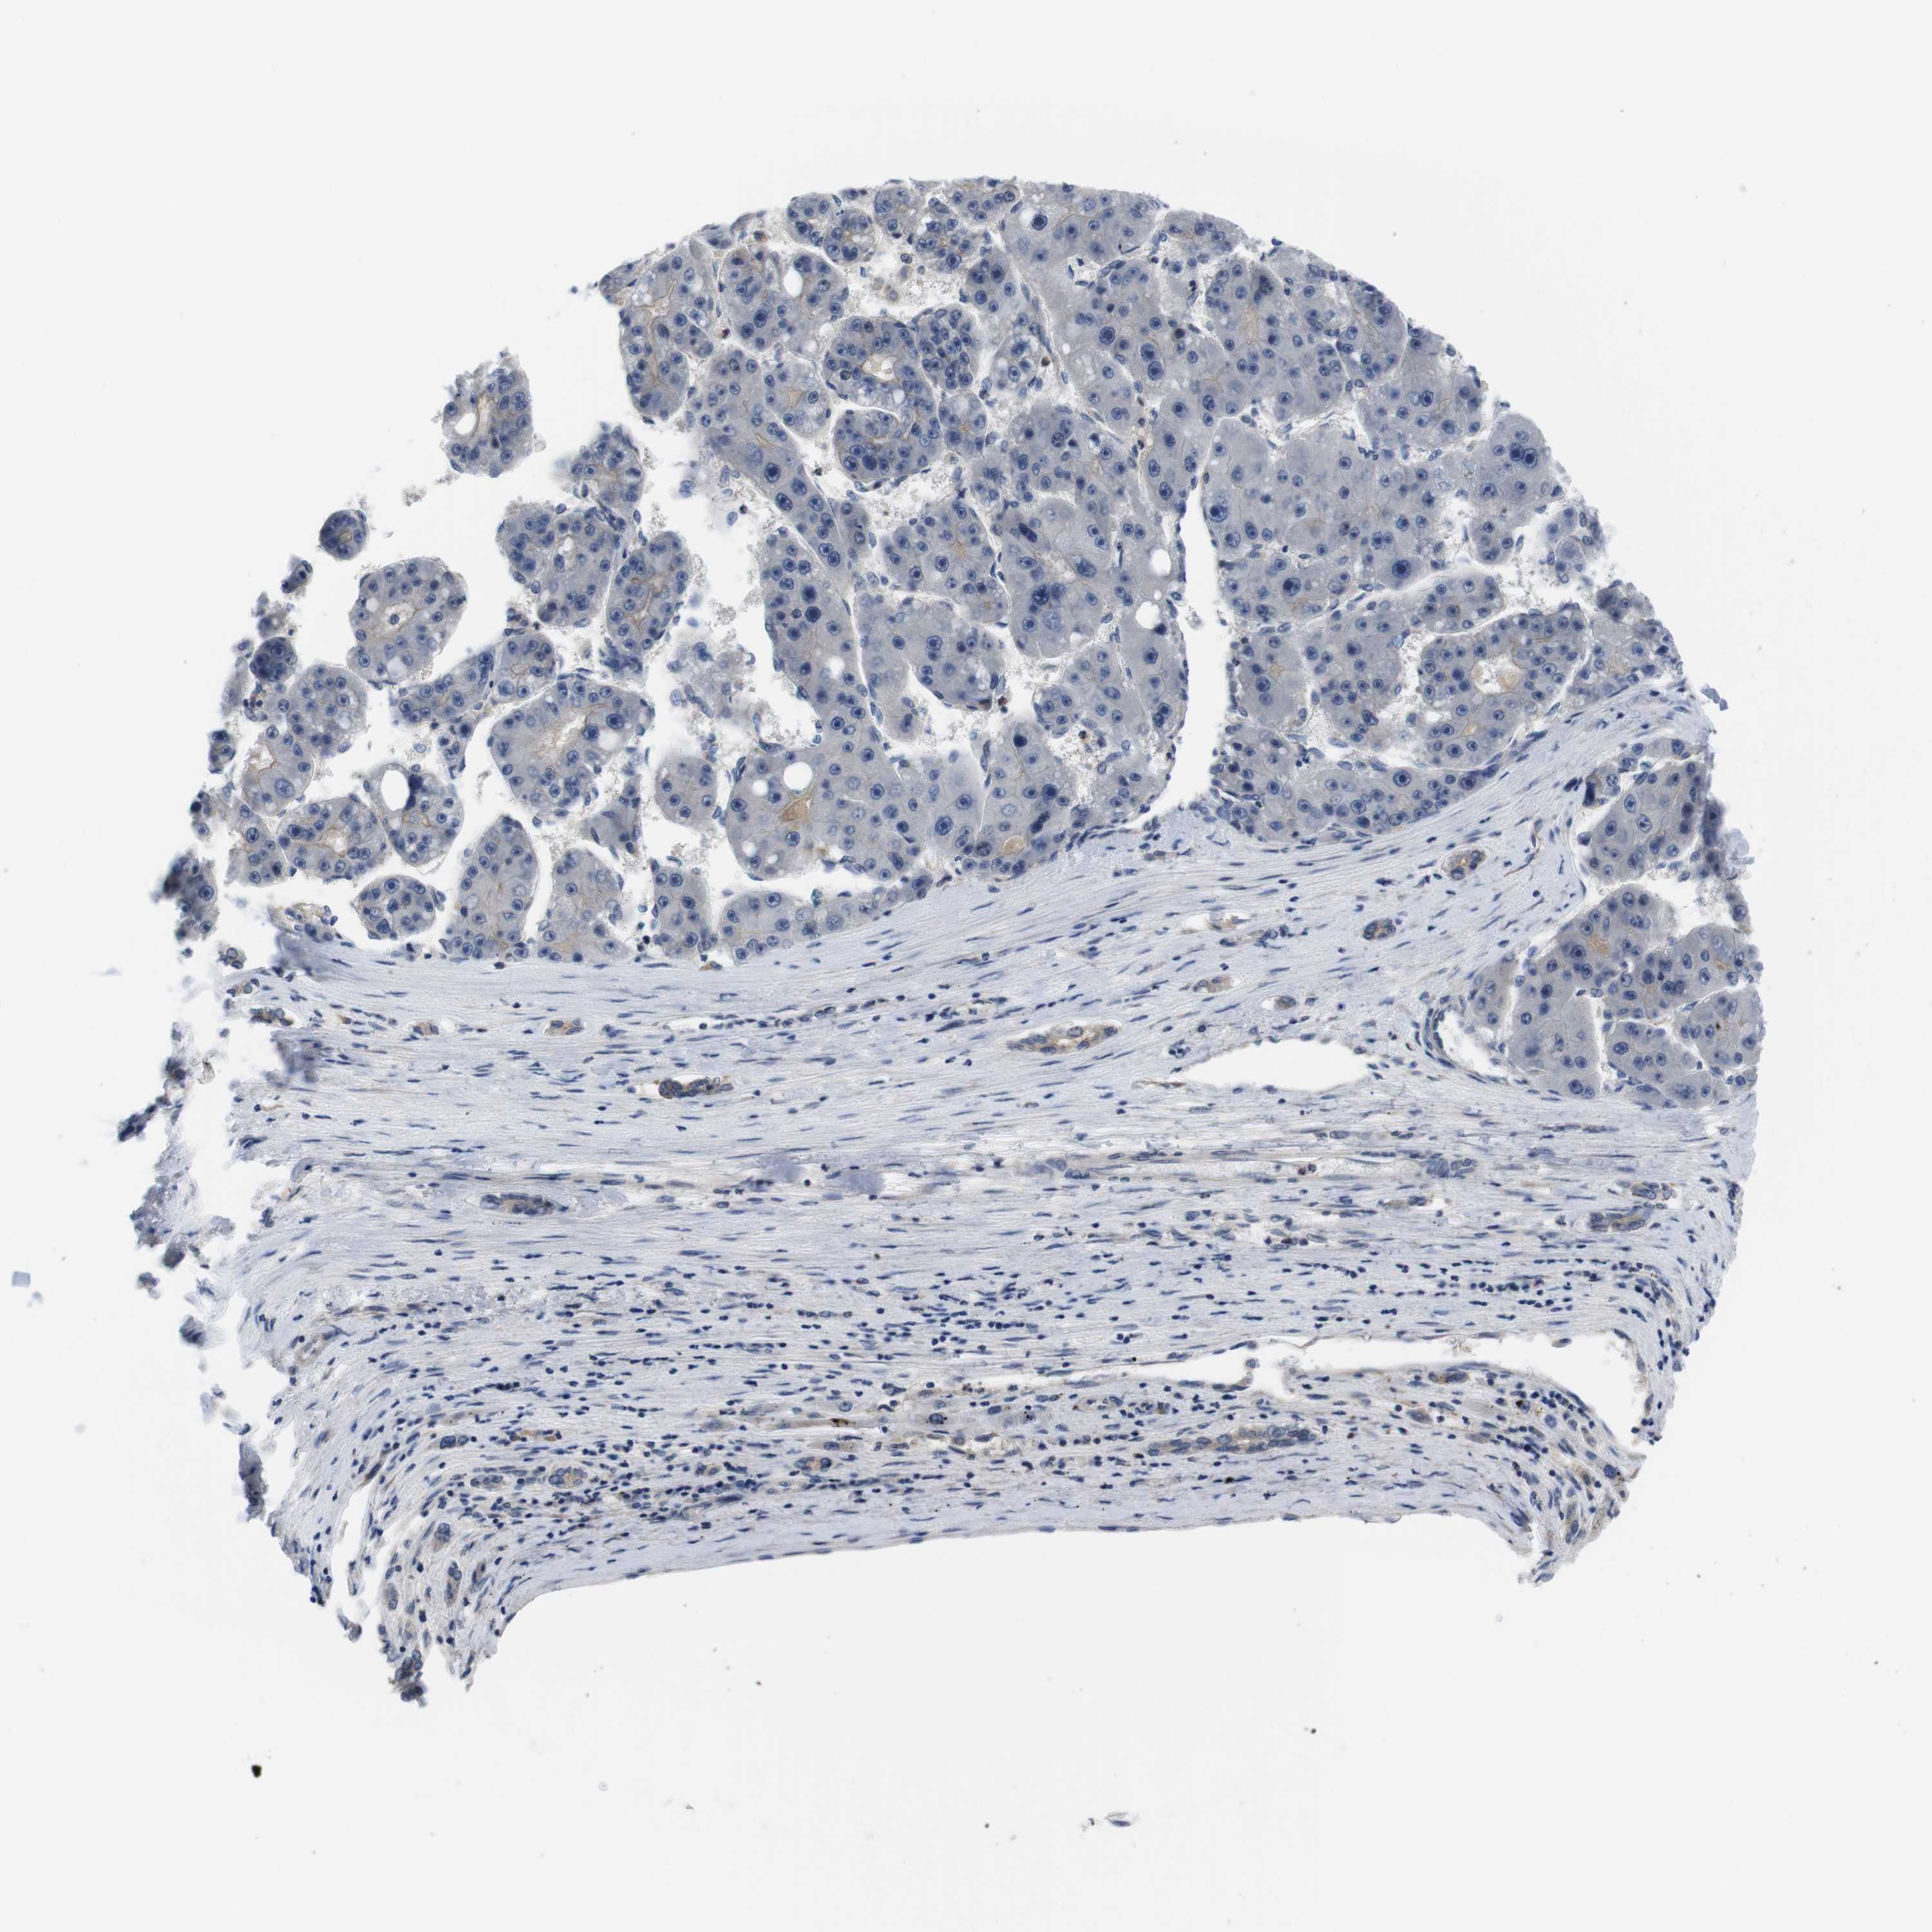

LIVER CANCER - Protein expressioni

A mouse-over function shows sample information and annotation data. Click on an image to view it in a full screen mode. Samples can be filtered based on level of antibody staining by selecting one or several of the following categories: high, medium, low and not detected. The assay and annotation is described here.

Antibody stainingi

Antibody staining in the annotated cell types in the current human tissue is reported as not detected, low, medium, or high, based on conventional immunohistochemistry profiling in selected tissues. This score is based on the combination of the staining intensity and fraction of stained cells.

Each image is clickable and will lead to virtual microscopy that enables deeper exploration of all samples and also displays staining intensity scores, fraction scores and subcellular localization as well as patient and tissue information for each sample.

Antibody HPA001464

Cholangiocarcinoma

Carcinoma, Hepatocellular, NOS